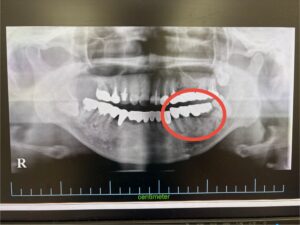

②矯正終了後、奥歯が噛み合わなくなる場合がある

マウスピース矯正は、常に表面をマウスピースで覆っている状態であり、奥歯をしっかり噛み締めることが出来ず、奥歯が下に下がってしまい奥歯が噛み合わなくなる場合があり、注意が必要です。